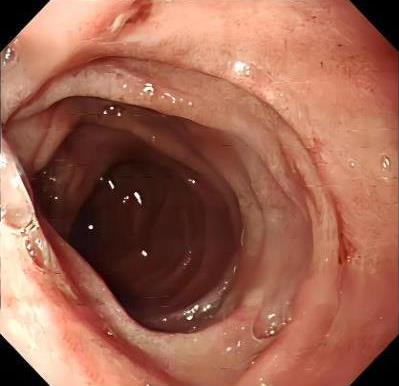

• 获得性免疫缺陷综合征合并马尔尼菲篮状菌导致肠道感染的内镜下表现(附6例报告)

2026, 32(3):84-88. DOI: 10.12235/E20250461

摘要 (32) HTML (27) PDF 3.50 M (26) 评论 (0) 收藏

摘要:目的 探讨获得性免疫缺陷综合征(AIDS)合并马尔尼菲篮状菌(TM)感染导致肠道感染的内镜下特征。方法 回顾性分析2022年11月-2024年10月于该院确诊为AIDS合并TM感染导致肠道感染的6例患者的临床资料。包括:临床症状、实验室检查、影像学检查、内镜检查和病理检查等。结果 6例患者中,男5例,女1例;发病年龄26~67岁;AIDS合并TM感染导致肠道感染患者的临床表现为:腹泻、腹痛、腹胀和恶心呕吐。其中,2例有消化道出血表现。实验室检查:6例患者外周血白细胞计数为(1.37~4.49)×109/L,血红蛋白计数为(67~99)g/L;CD4+T淋巴细胞为(1~52)个/μL,CD8+ T淋巴细胞为(61~321)个/μL,CD4+T淋巴细胞/CD8+T淋巴细胞比值为(0.01~0.18)。6例患者均行HIV RNA检测。其中,5例HIV RNA阳性。血培养:可见丝状真菌,报告显示为TM。影像学检查:6例患者CT结果可见肠系膜及腹膜后多发淋巴结肿大。内镜检查:6例患者内镜下均可见肠道病变。其中,十二指肠糜烂溃疡2例,结肠多发糜烂溃疡4例。病理检查:6例患者幽门螺杆菌(Hp)结果均为阴性,黏膜下可见成簇的小球形真菌孢子,符合TM感染;特殊染色:PAS(+),六胺银染色(+)。结论 当AIDS晚期患者出现消化道症状时,应警惕TM感染,病变部位常见于全结肠和直肠,亦可累及十二指肠,内镜下表现多为溃疡、糜烂和隆起性病变,形态表现无特异性;及时行胃肠镜检查、病理活检、特殊染色和免疫组化是确诊的关键。